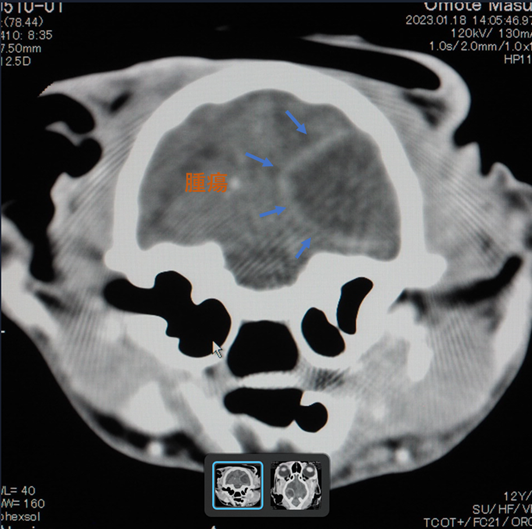

※診断書・CT画像 ( 病院より掲載の許可を得ています。)

水色の矢印内が腫瘍です。脳の3分の1以上の大きさになっています。